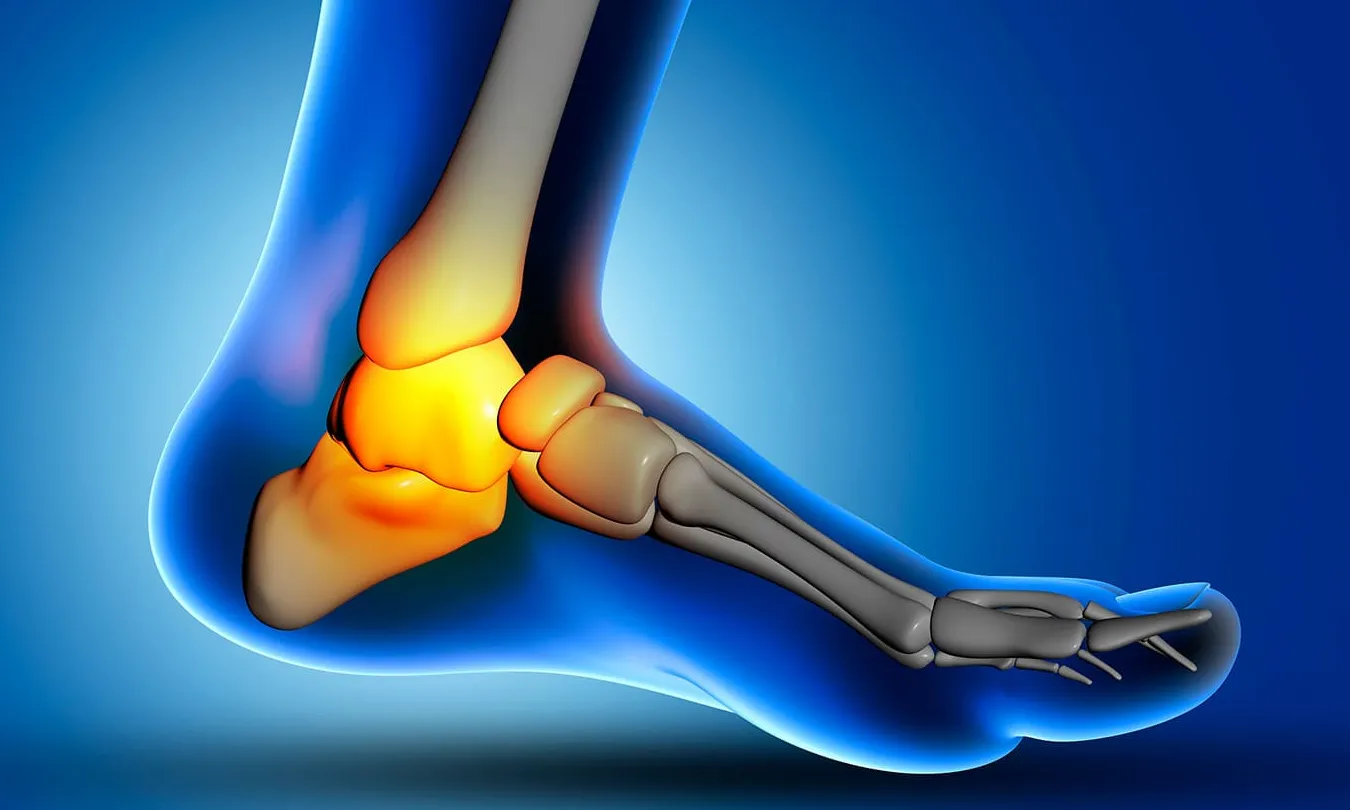

Entendiendo tu Tobillo: La Ingeniería Detrás de Cada Paso

Para comprender por qué duele, primero debemos apreciar la maravilla que es tu tobillo.

No es solo una bisagra;

es una compleja estructura de huesos, ligamentos y tendones que trabajan en perfecta armonía para soportar tu peso, absorber impactos y permitirte moverte con agilidad.

Está formado por:

- Huesos: La tibia y el peroné de la pierna se articulan con el astrágalo del pie, creando la articulación principal del tobillo.

- Ligamentos: Son como cintas resistentes que conectan los huesos entre sí, proporcionando una estabilidad crucial para evitar torceduras y luxaciones.

- Tendones: Unen los músculos de la pierna a los huesos del pie, permitiendo el movimiento activo de flexión, extensión y rotación. El más famoso es el tendón de Aquiles.

Cuando una de estas partes se daña o inflama, todo el sistema se resiente, y es cuando aparece el dolor.

Pero la buena noticia es que esta increíble estructura tiene una gran capacidad de recuperación si se le da el tratamiento adecuado.